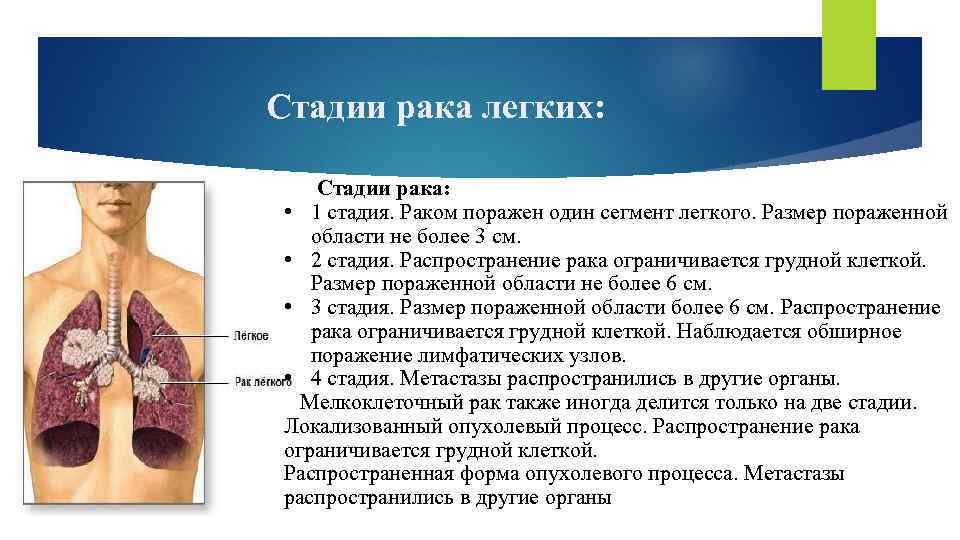

Стадии рака легких: Стадии рака: • 1 стадия. Раком поражен один сегмент легкого. Размер пораженной области не более 3 см. • 2 стадия. Распространение рака ограничивается грудной клеткой. Размер пораженной области не более 6 см. • 3 стадия. Размер пораженной области более 6 см. Распространение рака ограничивается грудной клеткой. Наблюдается обширное поражение лимфатических узлов. • 4 стадия. Метастазы распространились в другие органы. Мелкоклеточный рак также иногда делится только на две стадии. Локализованный опухолевый процесс. Распространение рака ограничивается грудной клеткой. Распространенная форма опухолевого процесса. Метастазы распространились в другие органы

Стадии рака легких: Стадии рака: • 1 стадия. Раком поражен один сегмент легкого. Размер пораженной области не более 3 см. • 2 стадия. Распространение рака ограничивается грудной клеткой. Размер пораженной области не более 6 см. • 3 стадия. Размер пораженной области более 6 см. Распространение рака ограничивается грудной клеткой. Наблюдается обширное поражение лимфатических узлов. • 4 стадия. Метастазы распространились в другие органы. Мелкоклеточный рак также иногда делится только на две стадии. Локализованный опухолевый процесс. Распространение рака ограничивается грудной клеткой. Распространенная форма опухолевого процесса. Метастазы распространились в другие органы